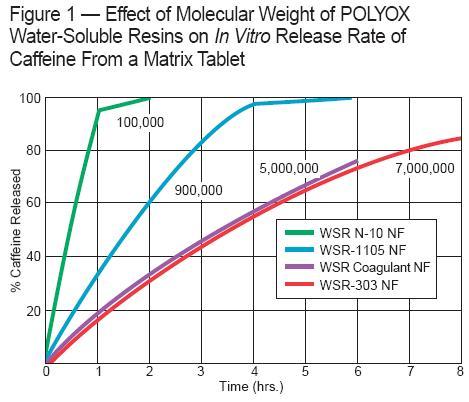

間質控釋之應用

POLYOX™於藥片表面快速水化形成包覆膠體層,藥物逐步經由包覆膠體中釋出,且藥物釋離率不受pH影響;

藥片配方中採用之分子量越大,藥物釋離通常越慢;

藥片配方中含量越高,藥物釋離也越慢,但藥物含量增加對藥物釋離率之影響並不顯著;

水溶與水不溶藥物均可配用此膠體,但特別適合應用於非水溶性藥物之間質控釋。